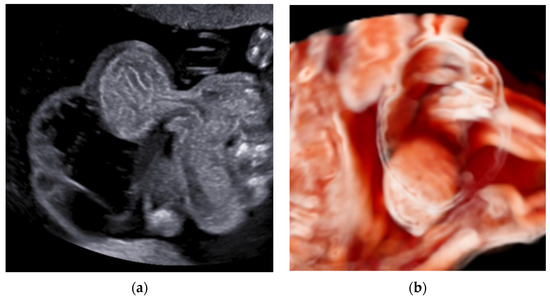

3.2. True Umbilical Cord Knot